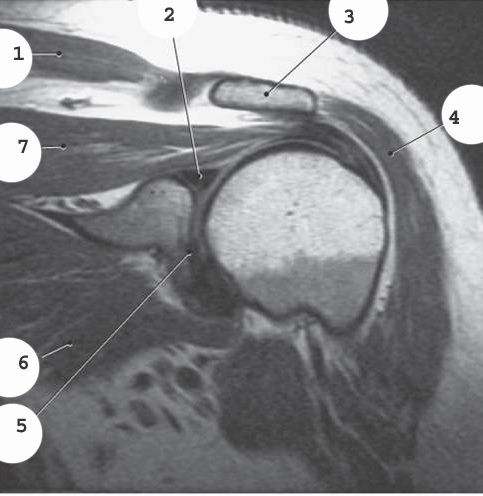

3

acromion

2

labrum

4

deltoid

5

glenoid

7

supraspinatis muscle

1

bicep